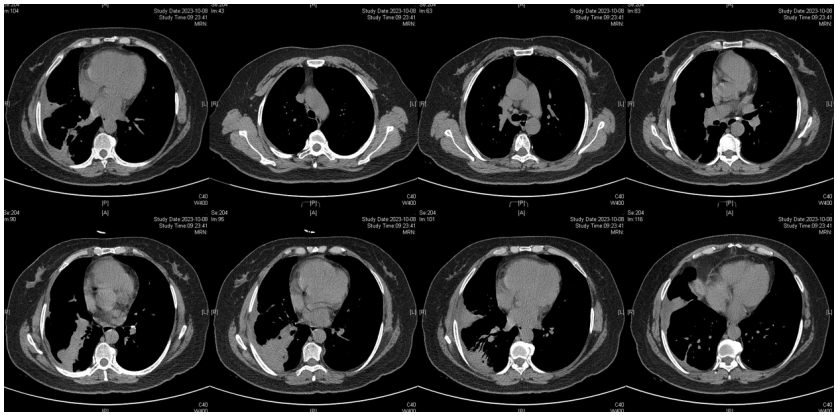

由于厌氧菌培养非常困难,既往我们对厌氧菌的认知仅限于在消化道定植,对其致病机制以及何种情况下致病并不非常清楚。厌氧菌定植于皮肤黏膜,是一种内源性微生物,感染发生率高,可导致严重、致死性感染。由于标本采集和转运的特殊性,使厌氧菌难以分离;加之其培养困难,体外生长慢,所以既往很难识别。厌氧菌在治疗方面存在一定挑战,如往往混合多重感染,且易产生耐药,也会因治疗延迟导致治疗失败。随着近10年来NGS技术的应用和普及,我们对厌氧菌的认识得以提升。常见的致病厌氧菌分为革兰阳性球菌、革兰阴性球菌、革兰阳性非芽孢杆菌、革兰阳性芽孢杆菌以及革兰阴性杆菌(表1)。革兰阳性非芽孢杆菌中可能致病的是放线菌,例如龋齿放线菌参与龋齿的发病过程。革兰阳性芽孢杆菌往往具有致病性,其中产气荚膜杆菌、艰难梭菌/难辨梭状芽孢杆菌、肉毒杆菌/肉毒梭菌、破伤风梭菌/杆菌具有强致病性。革兰阴性杆菌中的拟杆菌属对青霉素类药物具有很强的耐药性,易致青霉素治疗失败。临床中我们与厌氧菌的接触逐渐增多,对其特点也会愈发熟悉,对于临床诊断和治疗也会有所帮助。在NGS报告中通常会将检出的厌氧菌列为“C类”,定义为致病性C类—呼吸道正常微生态菌群,一般不导致感染。但当患者存在误吸风险时,需关注厌氧菌引起肺脓肿的可能。此时就需要针对患者的危险因素、临床表现、影像学、病原学以及气管镜下特点等进行综合分析。微小单胞菌最早是通过培养进行鉴定。瑞士2015—2022年132例病例报告的培养鉴定结果显示,血液中检出微小单胞菌37例(28%),肺内(肺脓肿、脓胸)检出29例(22%),总体病死率较低(5.3%)。国内周华教授团队开展的一项回顾性研究分析了2019年1月至2020年7月经病理活检和mNGS诊断的5例与微小单胞菌相关的慢性肺脓肿患者。患者的平均病程为6.5个月,共同特征是口腔卫生差,有酗酒史,且CT表现为边界不规则的高密度团块状实变影,并且在病灶中间可见液化性坏死,但没有发现气液平面或空腔,所以前期易被误诊为肺癌。下图1是该研究报告中病例3的肺部CT表现。时间点1:首次就诊时,左下叶可见团块状肺不张,伴周围磨玻璃样渗出病变,中心坏死不明显,可见细小空气囊泡影。时间点2:发病8个月时,可见大面积肺实变,增强CT示病灶内有液化坏死和小空洞。时间点3:经过3个月的有效抗厌氧菌治疗,病灶明显缩小,遗留空洞和纤维增殖病灶。图2是病例4的肺部CT表现。时间点1:患者首次就诊时,右上叶可见肿块样肺部实变影。时间点2:发病8个月时增强CT,可见实变明显增大,病灶内出现液化坏死。时间点3:经过3个月的有效治疗,病灶明显缩小,有残留空洞和纤维瘢痕样病变。由于通过影像学鉴别该病与肺癌具有挑战性,所以5例患者都接受了支气管镜检查和CT引导下经皮肺活检。5例患者经组织活检或支气管肺泡灌洗液(BALF)标本mNGS检测到微小单胞菌。病例: 女性, 67岁, 主诉"咳嗽咳痰2个月"。现病史:2个月前,患者家属感染新冠病毒(家属新冠抗原阳性)之后,患者出现咳嗽咳黄脓痰,无痰中带血及痰液拉丝,痰无臭味,无胸闷气短及胸痛,无咽痛咽痒,无鼻塞流涕。6月9日于当地市医院住院,住院期间出现发热,体温最高38.6℃,无寒战,查新冠病毒核酸阳性,予先诺特韦/利托那韦片口服治疗。查胸部CT见左肺上叶软组织影,左肺上叶炎症。诊断肺脓肿,予头孢唑肟联合莫西沙星,治疗后复查胸部CT(6月26日)病灶较6月9日明显吸收好转。6月14日气管镜检査见左肺上叶支气管开口狭窄,见大量脓性痰液堵塞支气管开口(病原学结果家属无法提供)。6月30日办理出院后仍有咳黄脓痰,无发热畏寒,口服止咳化痰药物,未使用抗生素。7月30日复诊胸部CT见左肺上叶异常密度较前增大。8月2日再次于当地市人民医院住院。8月4日气管镜检查: 左肺上叶黏膜肿胀肥厚, 管腔狭窄, 见大量白色干酪样分泌物涌出, 支气管镜不能进入。内科予莫西沙星静滴治疗10天, 外科予莫西沙星联合哌拉西林他唑巴坦静滴9天。复查胸部CT见病灶较前进展, 且右肺出现新发感染病灶。病程中患者饮食可, 睡眠差, 二便正常, 体重减轻5 kg。既往对阿莫西林过敏, 表现为口服阿莫西林后全身皮疹。否认嗜酒史及吸烟史。入院后胸部增强CT可见病灶内液化坏死,同时伴有小的空气囊泡影(图3)。患者有胸痛症状。气管镜检查发现气道内有痰栓或黏液栓阻塞征象(图4)。灌洗液tNGS结果回示:微小单胞菌(序列数2762),巨细胞病毒(序列数171),副流感病毒(序列数79),EB病毒(序列数61)。考虑病毒不会导致气道内如此改变,但由于微小单胞菌属于常见口腔定植菌,此时也不能完全确定微小单胞菌是否为引起感染的主要责任病原体。8月24日起予莫西沙星0.4 g qd ivgtt+哌拉西林他唑巴坦4.5 g q8h ivgtt。经过上述治疗,患者局部病灶有所吸收,但整个肺叶并无明显改善(图5)。气管镜检查仍然发现气道内有较黏稠的黏液栓阻塞气道开口(图6)。治疗经过:气管镜下予以局部冲洗,再次送检tNGS。9月7日结果回示:微小单胞菌(序列数6464),较前明显增多;副流感病毒(序列数998),EB病毒(序列数331)。9月9日起调整治疗方案为美罗培南1 g q8h。9月12日复查患者胸部CT,可见肺通气部分改善,肺组织内实变较前吸收(图7)。第三次气管镜检查仍可见少量痰栓嵌塞在远端支气管开口(图8)。患者此后转入医联体医院继续抗感染治疗。病例2:女性,54岁。主诉:咳嗽咳痰2个月,发热1周。现病史:入院2个月前,患者在西南地区旅游时感冒,出现咳嗽咳痰,白痰为主,量多,无胸痛,无发热,无痰中带血,咳时气短。于河北某诊所间断输液治疗14天(具体不详),期间口服中药治疗,症状未缓解。入院3周前(2023-09-07)就诊于当地县医院,查胸部CT提示右肺炎症,静脉滴注氨曲南、左氧氟沙星、氨溴索治疗1周,症状未缓解。2023年9月14日复查胸部CT显示右肺炎症较前加重,于当地中心医院住院。动脉血气分析:pH 7.43,PaCO2 38.4 mmHg,PaO2 67 mmHg,SaO2 94.2%;血沉90 mm/h;生化:白蛋白35.3 g/L;CRP 82.7 mg/L;血常规:WBC 9.75×109/L,NEU 6.83×109/L,HGB 104 g/L。静脉滴注莫西沙星。入院10天前,行肺穿刺活检,病理回报为少量肺组织及纤维结缔组织,炭末沉积,较多中性白粒细胞、淋巴细胞及浆细胞浸润,伴脓肿形成;肺穿刺mNGS结果回报:微小单孢菌(序列数2650),鲍曼不动杆菌(序列数17),人类疱疹病毒4型(序列数60),人类疱疹病毒7型(序列数5),文氏密螺旋体(序列数4337),解卵磷脂密螺旋体(序列数1121),齿垢密螺旋体(序列数698)。调整抗生素为头孢哌酮舒巴坦2 g q12h。入院1周前,出现发热,体温最高38.5℃,不伴寒战,咳嗽咳痰无加重,无咯血;复查血常规、PCT、CRP均明显增高(未见报告单);复查胸部X线提示右肺炎症范围增大,右侧胸腔积液。更换抗生素为哌拉西林他唑巴坦4.5 g q8h。4天前,支气管镜下见右肺下叶背段支气管略狭窄,黏膜水肿,可见脓性分泌物溢出。BALF革兰染色查见革兰阴性杆菌,抗酸染色、霉菌未见异常,培养未回报。患者体温逐渐降至正常,咳嗽咳痰有所减轻,复查胸部CT提示右肺高密度影,右侧胸腔积液较前增多。为求进一步诊治来我院就诊被收入院。既往甲状腺功能减退病史5年,目前口服优甲乐治疗,监测甲状腺功能指标在正常范围。20年前因宫外孕行手术治疗。2023年10月8日胸部CT示胸膜下斑片状坏死,纵隔窗可见微小空气囊泡影及密度不均匀液化坏死(图9)。治疗:9月28日至10月13日莫西沙星0.4 g qd ivgtt+哌拉西林他唑巴坦钠4.5 g q8h ivgtt。最终患者病灶吸收好转并顺利出院。患者男性,42岁。主因间断咳嗽、咳痰1月余,左侧胸痛、气短2天入院。现病史:入院前1月余(2022-07-19),患者无明显诱因出现咳嗽,咳白痰,痰中有少量鲜红色血丝,左侧胸痛(为钝痛),深吸气后加重,就诊于当地医院。完善肺动脉CTPA:示左上肺动脉舌段分支局部管腔可见线条样低密度充盈缺损,考虑肺栓塞;左肺上叶实性病变伴不均匀强化,性质待定,部分为肺梗死改变可能,纵隔多发稍大淋巴结,性质待定;右肺下叶后基底段可见一不规则实性结节,边缘可见多发毛刺,直径约0.7 cm。当地医院考虑肺栓塞不除外,肺部感染?右肺下叶结节,予莫西沙星抗感染,低分子肝素抗凝,乙酰半胱氨酸化痰。完善CT引导下肺穿刺活检,病理示:肺泡腔扩张伴上皮轻度增生,肺泡间隔纤维组织增生伴散在炎细胞浸润,未见恶性病变。院外规律应用甲磺酸艾多沙班60 mg bid抗凝,先后间断应用左氧氟沙星0.5 g qd、头孢类抗生素(具体药物、剂量不详)抗感染。患者仍有间渐咳黄白痰,量不多,痰中有少量鲜红色血丝;无畏寒、发热、胸痛、夜间阵发性呼吸困难症状,无尿少、双下肢水肿,无口干、咽干,无牙齿成片脱落,无晨僵、关节肿痛,周身无皮疹,无盗汗乏力。2天前(2022-09-16)患者无明显诱因再次出现左侧胸痛,疼痛剧烈,深吸气、咳嗽及改变体位时加重,伴气短,就诊于我院急诊。完善肺动脉CTPA:肺动脉主干及其各叶段分支未见明显充盈缺损,左肺上叶舌段团块影,最大截面约7.6 cm×5.3 cm,边界不清,周围可见晕征;增强扫描不均匀强化,邻近胸膜增厚,性质待定,建议穿刺活检;纵隔及左肺门多发淋巴结显影。血细胞分析:WBC 11.09×109/L,NEU% 80.8%,NEU 8.95×109/L;CRP 54 mg/L,PCT 0.07 ng/ml。患者自发病以来,精神状、食欲及睡眠均一般,大小便正常,体重下降5 kg。2022年9月14日外院胸部增强CT:胸膜下楔形的影像学表现可见少量小气泡囊以及液化坏死病灶(图10)。初始考虑肺部肿瘤及肺栓塞。经过初步抗感染及抗凝治疗,患者病情无缓解,2022年9月27日患者突发胸痛,下肺影像加重并且出现脓胸(图11)。行胸腔穿刺并将脓液送检mNGS,结果回报:牙龈卟啉单胞菌(序列数3)。尽管序列数很低,但考虑是脓肿穿刺结果,因此考虑该菌致病可能。抗厌氧菌治疗:9月16-28日莫西沙星0.4 g qd ivgtt,9月23日-10月12日美罗培南1 g q12h ivgtt,9月28日-10月8日万古霉素1 g q12h ivgtt,10月13-18日莫西沙星0.4 g qd ivgtt+甲硝唑0.5 g tid ivgtt。患者肺脓肿的整体治疗时间约为3个月,病灶逐渐吸收,最终形成一些纤维索条影(图12,图13)。1年后复查病灶基本吸收(图14)。图14 1年后复查胸部CT(2023-08-08)微小单胞菌和卟啉单胞菌这两种厌氧菌在临床中需要引起重视,它们容易引起肺脓肿/脓胸。2024年国内学者Li Yao等在Diagn Microbiol Infect Dis 杂志发表了一篇牙髓卟啉单胞菌感染所致肺脓肿的病例报告,文章也提到在胸水或肺组织活检中,通过mNGS同时检出了微小单胞菌和卟啉单胞菌感染引起的肺脓肿。文章还回顾总结了既往发表的厌氧菌感染引起肺脓肿的病例,2010年报道的是1例脑脓肿患者,2019年报道1例脑炎患者,2022年报道1例脓胸伴呼吸衰竭患者。3例患者预后都比较好,可见厌氧菌亦可导致肺外多部位感染。对于厌氧菌所致肺脓肿的诊断及其引起的脓胸,目前的文献报道仍然较少,我们对它们的认知也有限,因此也提醒大家关注相关疾病的诊断和治疗。我们也已将本研究小组8例微小单胞菌所致肺脓肿的系列病例的研究结果发表(Front Cell Infect Microbiol, 2024, 14: 1416884),可供需要的同行参考。对于厌氧菌感染,我们需要提高警惕。厌氧菌往往在口咽部定植,其引起的脓肿/感染往往多为亚急性或慢性起病。患者通常有发热、胸痛症状,脓肿会逐渐进展。由于厌氧菌与人体本身是一种长期共生的关系,人体对厌氧菌的免疫识别可能处于较低的防御反应状态,所以会形成一个亚急性或慢性的发病过程。通常情况下,因厌氧菌的菌群发生了移位,从卫生条件不好的口腔扩展到相对无菌的肺内,同时开始增殖,由此可能导致感染。因此,对于酗酒以及口腔卫生非常差的人群,我们要重视对其风险因素和病史的排查。患者就诊时可能病情并不重,有胸痛或咯血,很容易误诊为肺部肿瘤,往往在这种情况下进行肺穿刺或气管镜检查,mNGS可以发现较大序列数的厌氧菌。但在mNGS检出厌氧菌后的诊断过程中又容易形成误判——究竟是致病菌,还是定植菌?此时结合患者其他病史和影像学特点(有脓肿/痰栓形成,微小空气气囊泡影),可能提示厌氧菌感染。然而,厌氧菌感染在病原学和影像学诊断方面仍然存在诸多困难,极易漏诊和误诊。微小单胞菌感染患者在气管镜下可以看到典型的脓性分泌物嵌塞气道,导致气道阻塞,也会造成远端气道和肺泡引流障碍。所以,及时处理气道内痰栓,改善引流,可能是使患者获得良好预后的关键。厌氧菌肺脓肿的吸收比较缓慢,抗感染的疗程也比较长,需要在后期诊疗过程中密切随访和观察患者对治疗的反应以及耐药等问题,及时调整治疗方案,适当延长疗程。